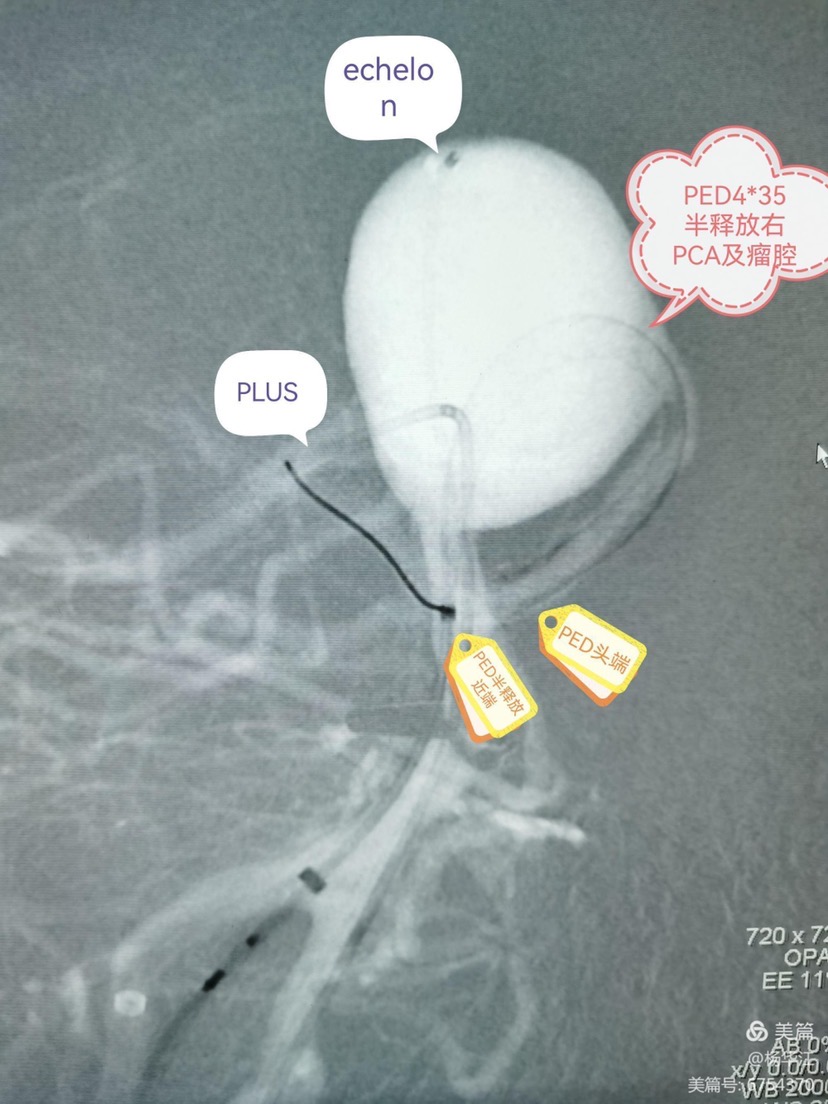

先echelon10微导管瘤内成襻技术超选入右侧大脑后动脉远端,拉直解襻微导管,交换phenom导管到右侧大脑后动脉远端,由于瘤颈超宽,导管再次疝入成襻才能超选至右侧大脑后动脉远端。

换第二个工作角度,prowlerplus微导管顺利超选至左侧大脑后动脉远端,echelon栓塞导管置于瘤腔内。

4.0x35pipeline经成襻的phenom导管缓慢送人右侧大脑后动脉远端,锚定,缓慢半释放至基底动脉中上段。